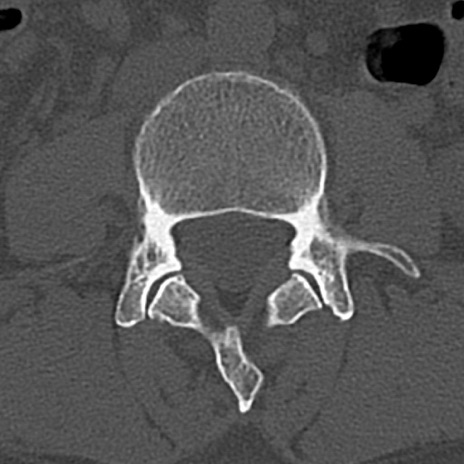

腰椎CT

横断像と矢状断像